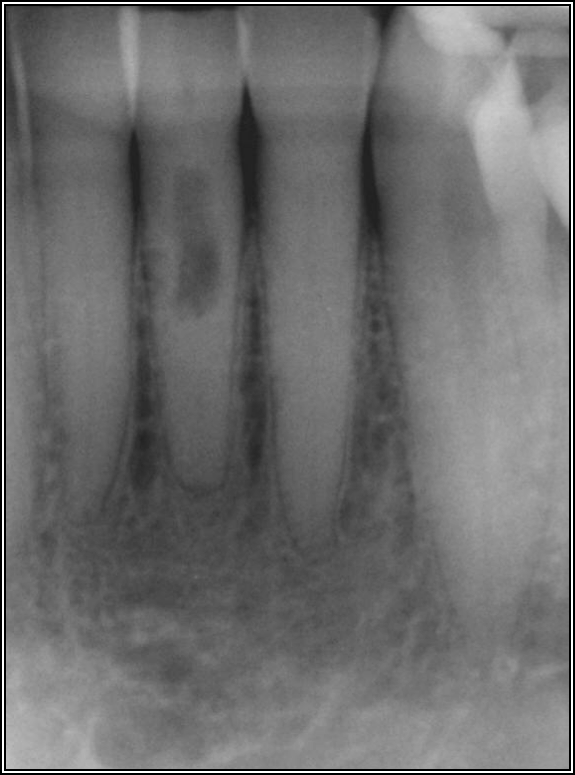

As to which material to use, the literature indicates fiber is better because it has greater flexibility and is less likely to allow for vertical fractures.2,3 It also has better esthetics, which is significant for both anterior and posterior teeth. The problem with fiber posts is that they can snap off and pull out. When they snap off, they are difficult to remove. A tapered diamond bur or ultrasonic can be used, but it must be done very carefully. Depending on the circumstances, metal can also be difficult, but metal is often serrated or threaded and can be unwound with an ultrasonic. However, fiber is significantly more flexible because it has a better modulus of elasticity, which should be as close to the dentin's elasticity as possible. On the radiograph, it can be difficult to see. Figure 17 shows a case with a good fiber post on the lateral that could be longer. The central should definitely be longer than it is. Because the clinician thought the posts and crowns were well done with good seals, when the patient had pain and apical radiolucencies, they were treated with apicoectomies. This was easier and less invasive than dismantling the previous structure.

Fig 17. A case with a good fiber post on the lateral that could be longer.

Figure 17